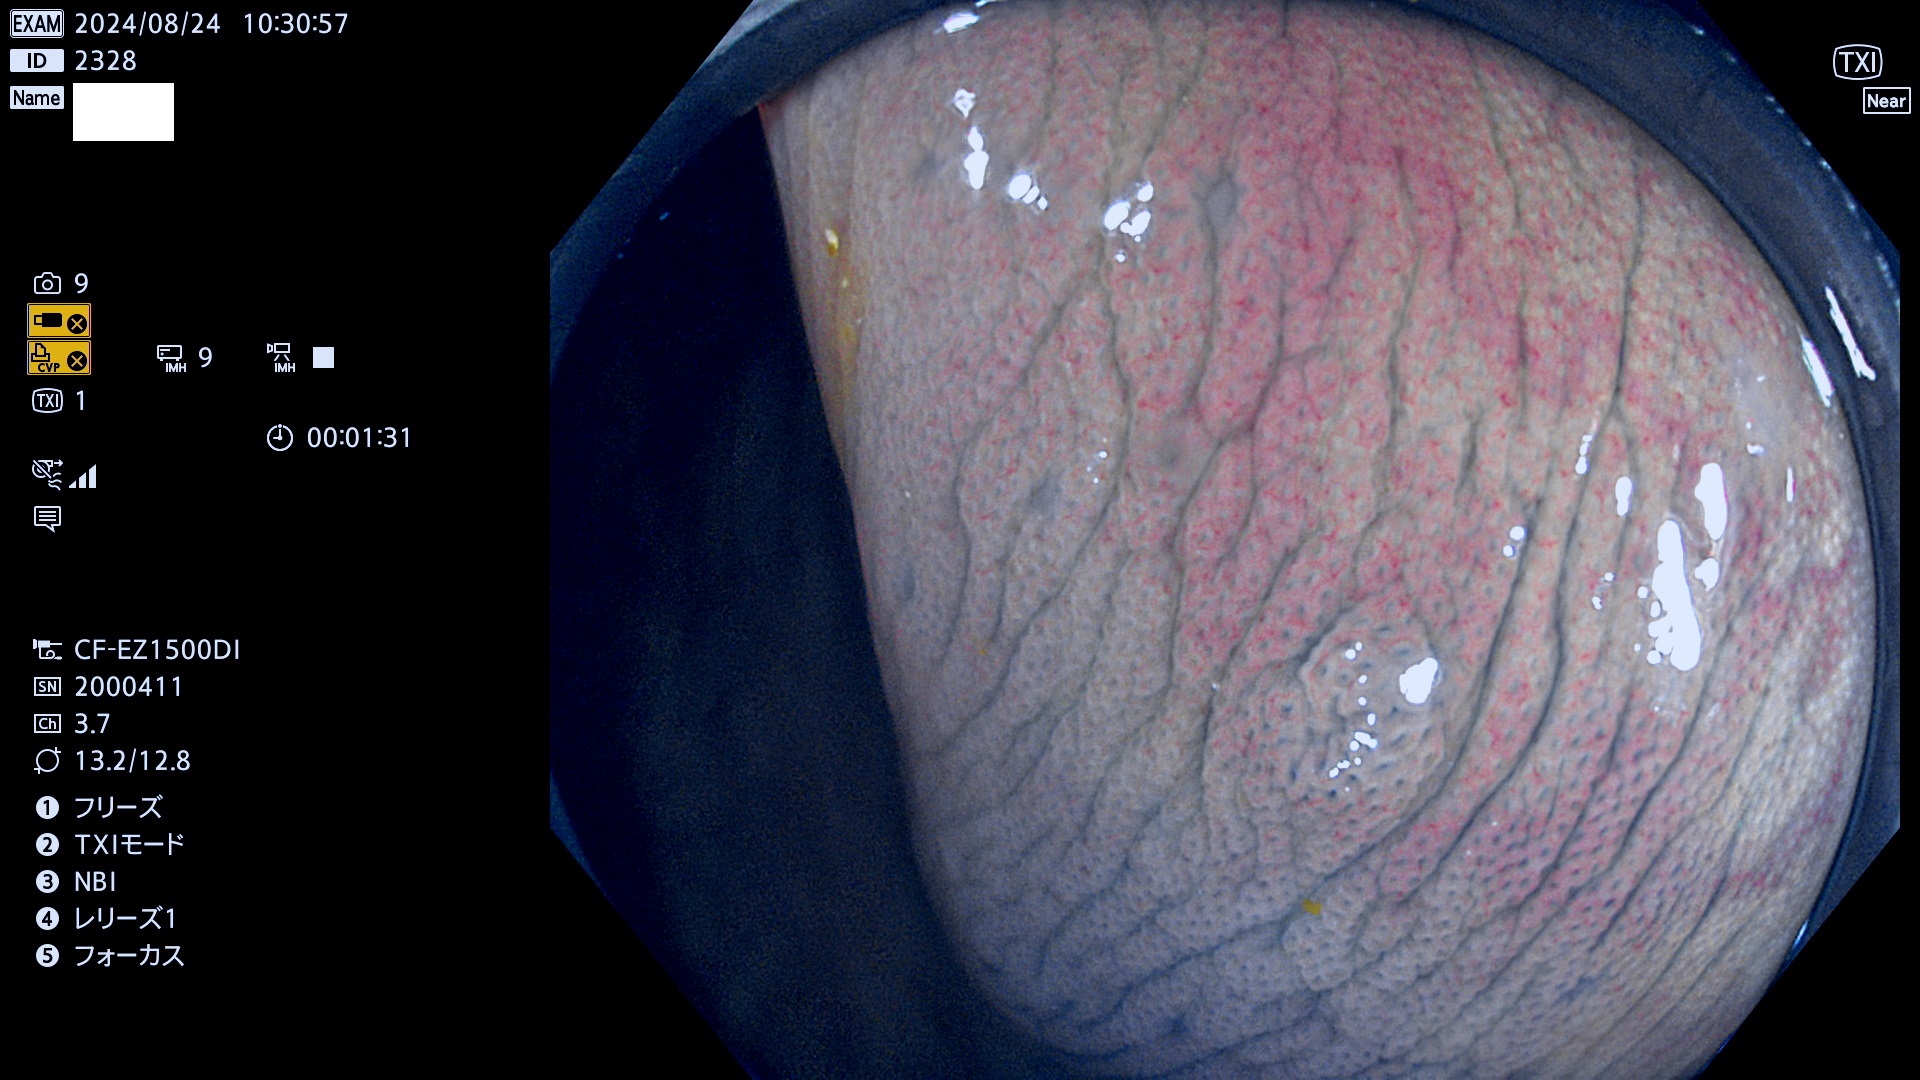

完全に平坦な物をUb、陥凹している物をUcと呼びます。最も発見が難しく危険な病変です。

毎週の検査(木・金・土・日)に発見されたUb、Uc型・腺腫を、その週の日曜の夜にUPし1週間、提示します。

抽出の対象期間 2024年8月22日〜8月25の4日間(33件の検査)7件 (7/33=21%)